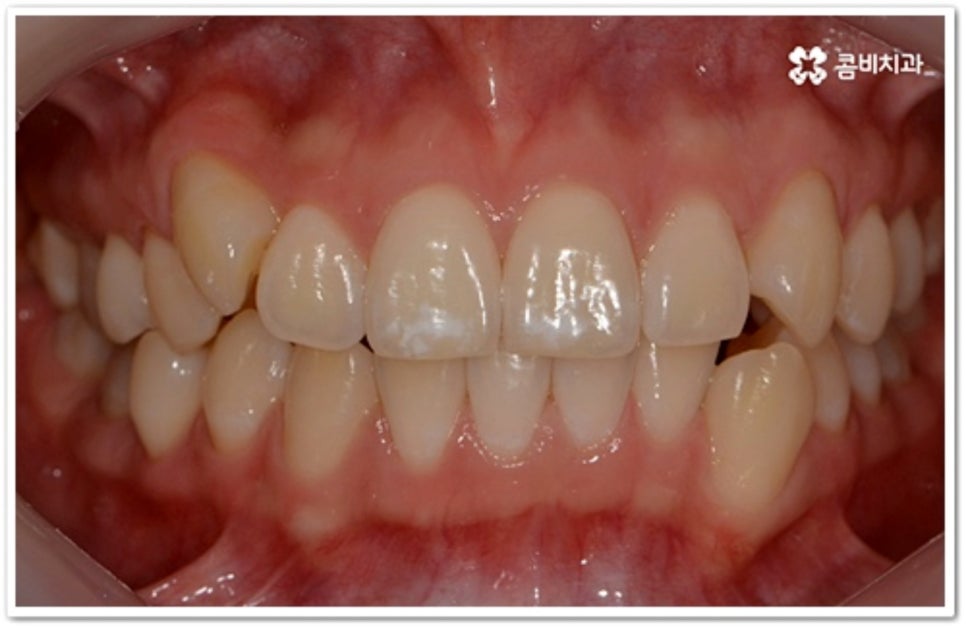

출처 아카이브 열기부정 교합의 일종인 덧니는 사람마다 다양한 원인으로 인해 발생하지만 보통 치아가 나올 공간이 부족하거나 치아 크기가 많이 커서 자기 자리에서 똑바로 나오지 못하고 이미 자리를 잡은 치아 앞 또는 뒤로 겹쳐 나오게 되면서 생기는 경우가 대부분이라고 할 수 있어요. 웃을 때 덧니가 살짝 드러나면 귀여운 인상을 주지만 실생활에서는 겹쳐진 치아 사이로 음식물이 자주 끼어 구강 질환을 유발하거나 저작 기능이 저하되는 등 불편함을 초래할 수 있습니다. 그렇기 때문에 치아 교정을 통해 가지런한 치열로 바로 잡아주실 필요가 있는데요.

이때 덧니 교정 시 치아를 뽑는 과정이 필수적인지 궁금하신 분들이 있을 거예요. 환자분들마다 상황이 다르기 때문에 획일적으로 말씀드리기는 어렵겠지만 다양한 기술을 이용한 비발치 교정 치료도 가능하기 때문에 먼저 꼼꼼한 검진 및 충분한 상담을 통해 자신에게 맞는 치료 계획이 무엇인지 알아보시길 권유드리고 있습니다. 예를 들어 입 속 공간은 크게 부족하지 않은데 악궁만 상대적으로 좁은 경우 확장 장치를 이용하여 이를 벌려주는 방법을 통해 치아를 발치하지 않고 교정 치료를 진행할 수 있어요. 덧니가 심하지 않고 치아 크기가 큰 경우 치간 삭제를 통해 조화를 맞추고 빈 공간을 확보하여 치아를 가지런하게 배열하는 방법도 있습니다.

그러나 만약 덧니가 많고 부정 교합 정도가 심하거나 치아가 고르게 배열될 공간이 크게 부족하다면 덧니 발치 교정 치료를 진행하게 되는데, 이때 보통 치아 중에 기능이 가장 적은 소구치를 우선적으로 발치하게 되지만 (사진에서 확인할 수 있는 케이스) 환자분들의 상황에 따라 필요 없는 사랑니를 발치하고 어금니부터 뒤로 밀어 자리를 잡아주거나 충치 또는 짧아진 치근 등으로 심하게 손상된 치아가 있는 소구치를 우선적으로 발치하여 교정 치료를 진행하기도 하고, 필요시 임플란트와 병행하여 치료를 진행하는 경우도 있습니다. 따라서 먼저 자신의 상황에 대해서 면밀하게 검진을 받아보고 자세한 치료 계획에 대해서 의료진과 충분하게 상담해 보시는 게 좋을 거예요.